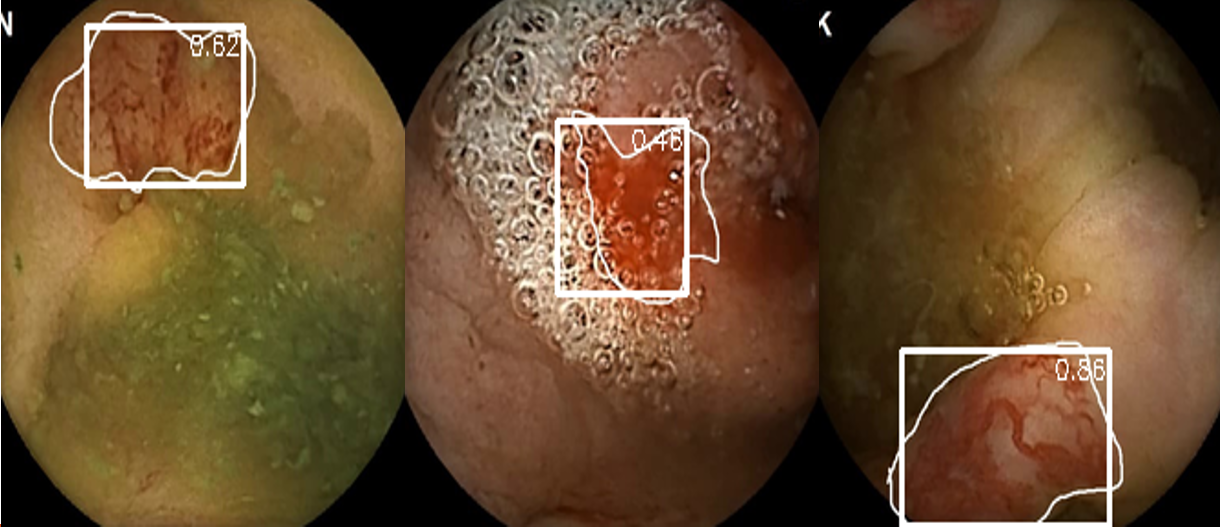

Refer to caption

Figure 2: Examples of successful bleeding detection from our validation dataset, showing the model’s ability to identify different types of GI bleeding.